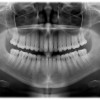

Rontgen gigi panoramik, atau biasa disebut dengan Orthopantomograph (OPG), adalah sebuah prosedur atau teknik pengambilan radiograf pada area maksila dan mandibula yang banyak digunakan misalnya untuk evaluasi gigi impaksi dan penegakan diagnosis kanker rongga mulut. Gambaran yang dihasilkan dari pengambilan teknik radiograf ini adalah dua dimensi, mencakup area telinga kanan hingga telinga kiri, area infraorbital dan bagian bawah mandibula.[1]

Indikasi dari penggunaan prosedur ini adalah untuk melihat gigi impaksi; perawatan orthodonti baik sebelum dan sesudah perawatan; dan penilaian derajat kehilangan struktur tulang dan jaringan periapikal. Rontgen gigi panoramik juga digunakan untuk penentuan penempatan dental implan; menentukan sumber nyeri akibat gigi; penegakan diagnosis anomali pertumbuhan dan perkembangan gigi pada anak serta remaja; hingga penegakan diagnosis kanker rongga mulut.[1,2]